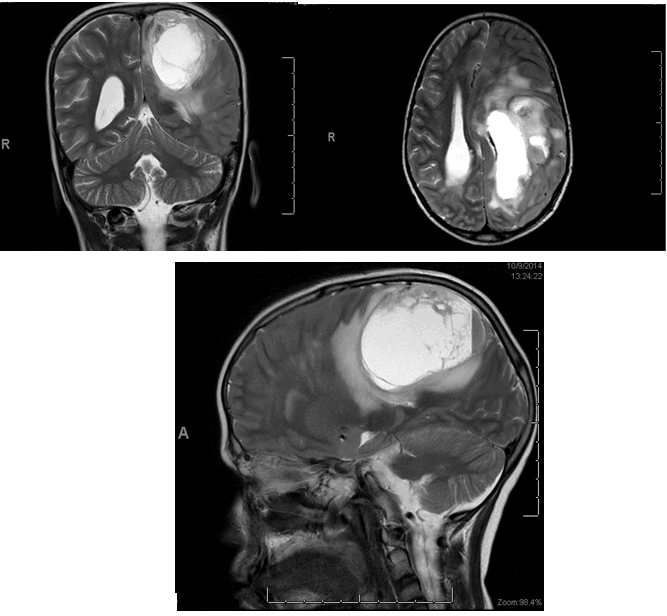

In 2014, the child presented with severe headache, projectile vomiting, blurring of vision, increased weakness and poor appetite. His symptoms and signs were suggestive of increased intracranial tension, so we requested full investigations to exclude the recurrence of the initial disease including bone marrow aspirate which was normal. We requested also MRI scan of brain and spine which was done during his admission and showed a large supratentorial multi-loculated mass suggestive of brain tumor versus brain abscess (Figure 1).

Figure 1: Magnetic resonance imaging scan of brain showing a large supratentorial multi-loculated mass lesion mainly cystic with fluid-fluid level occupying the left high parietal lobe, associated with significant surrounding brain edema causing mass effect and shift of midline structure with subfalcine/uncal herniation with a noted mass effect on ipsilateral lateral ventricle.